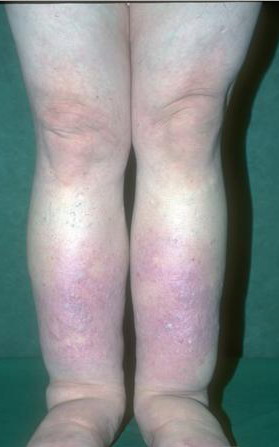

Acquired lymphedema is often painless and leaves legs feeling heavy and the patient tired. Although the limb swells during the day, indentations from socks can be seen on the leg at nighttime, returning toward normal during the night, but the leg stays swollen, and initially concerns may be cosmetic in nature. The foot is often involved first and initially lesions pit with pressure. With time, lesions become woody or lardaceous and do not pit. The toe contours are lost . Kaposi-Stemmer sign, a feature of chronic lymphedema, describes the skin over the proximal digit of the second toe that cannot be elevated; in edema the skin can be elevated.

Prolonged lymphedema leads to fibrosis and epidermal hyperplasia with verrucous hyperkeratosis (Fig. 175-10). Ulceration rarely occurs, although the edema and hyperkeratotic changes may be profound. Lymphangiosarcoma, the Stewart-Treaves syndrome when associated with postmastectomy lymphedema, is the common lesion in chronically lymphedematous locations .